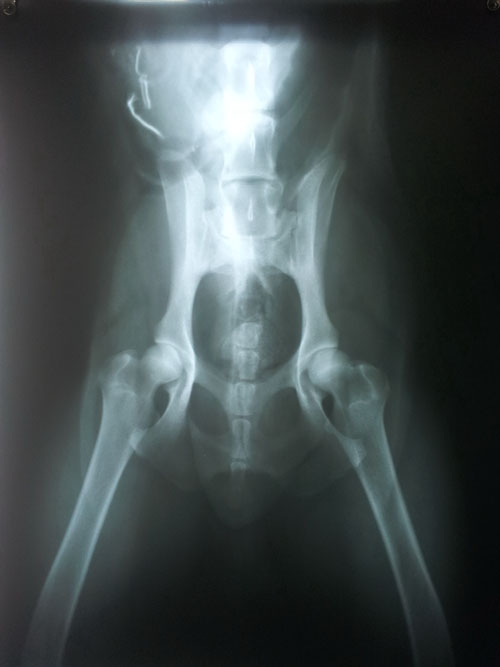

Donmoon Baron Boeing แกลเลอรี่ส่วนตัวของพ่อและแม่ คู่ผสมพันธุ์ที่พิสูจน์แล้วว่าให้ลูกที่มีข้อสะโพกปกติ

HD - Normal ทุกตัว